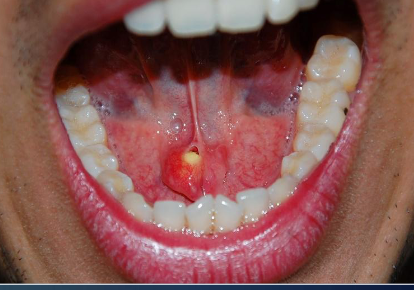

mucocele

most common on lower lip due to trauma of minor salivary gland